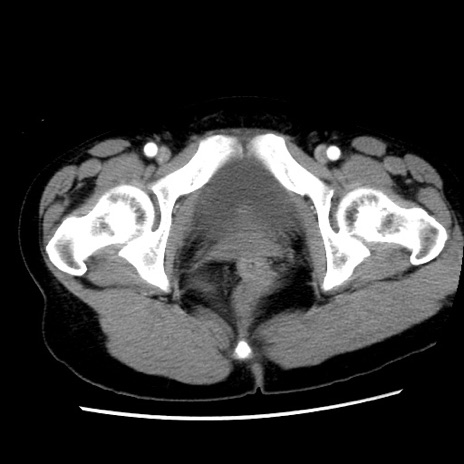

症例10(横断像)

【症例】 50歳代女性

【主訴】 腹痛

【現病歴】前日生レバーを食べた。今朝に排便あり。 昼前に突然発症の腹痛を生じ、当院救急外来を受診した。

【既往歴】 子宮筋腫にてで子宮全摘後

【身体所見】 意識清明、腹部:平坦、軟、下腹部やや左を中心に圧痛・反跳痛あり、筋性防御あり

【データ】WBC 7800、CRP 0.07